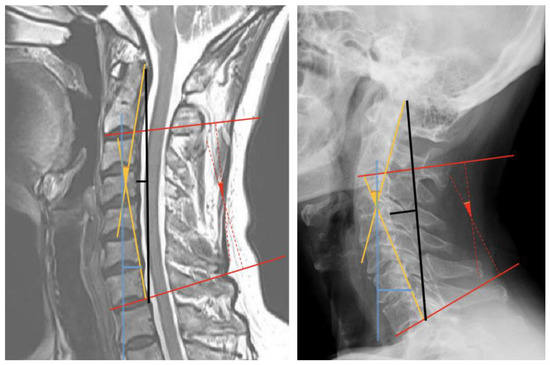

2.2. Measurements